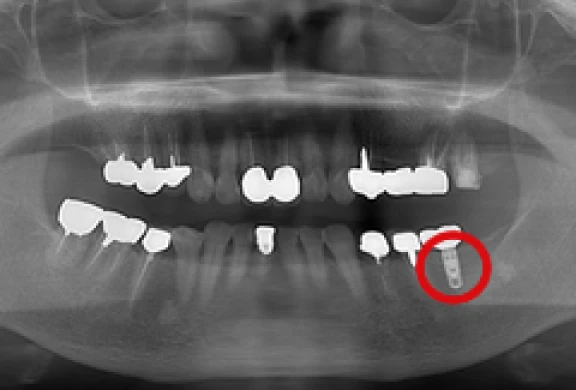

インプラント

自分の歯のような噛み心地を

歯科用CTによる精密診断を行い、お口の中の状態をしっかり把握させていただいた上で、適応のある方は院内にてインプラント治療を行います。

歯を失って再びご自身の歯のような噛み心地をご希望の方は、ご相談いただきたいと思います。

- 歯科用CT(タカラベルモント社BEL-X(ベルクロス))を設置しています。当院で撮影・画像診断を行い、院長自らが手術を行いますので、安心してご相談下さい。

- 当院ではHA(ハイドロキシアパタイト)インプラントを採用しています。

パノラマ

-

歯間部のインプラント

(2本)

(2本、上部構造の装着)

上顎のインプラント